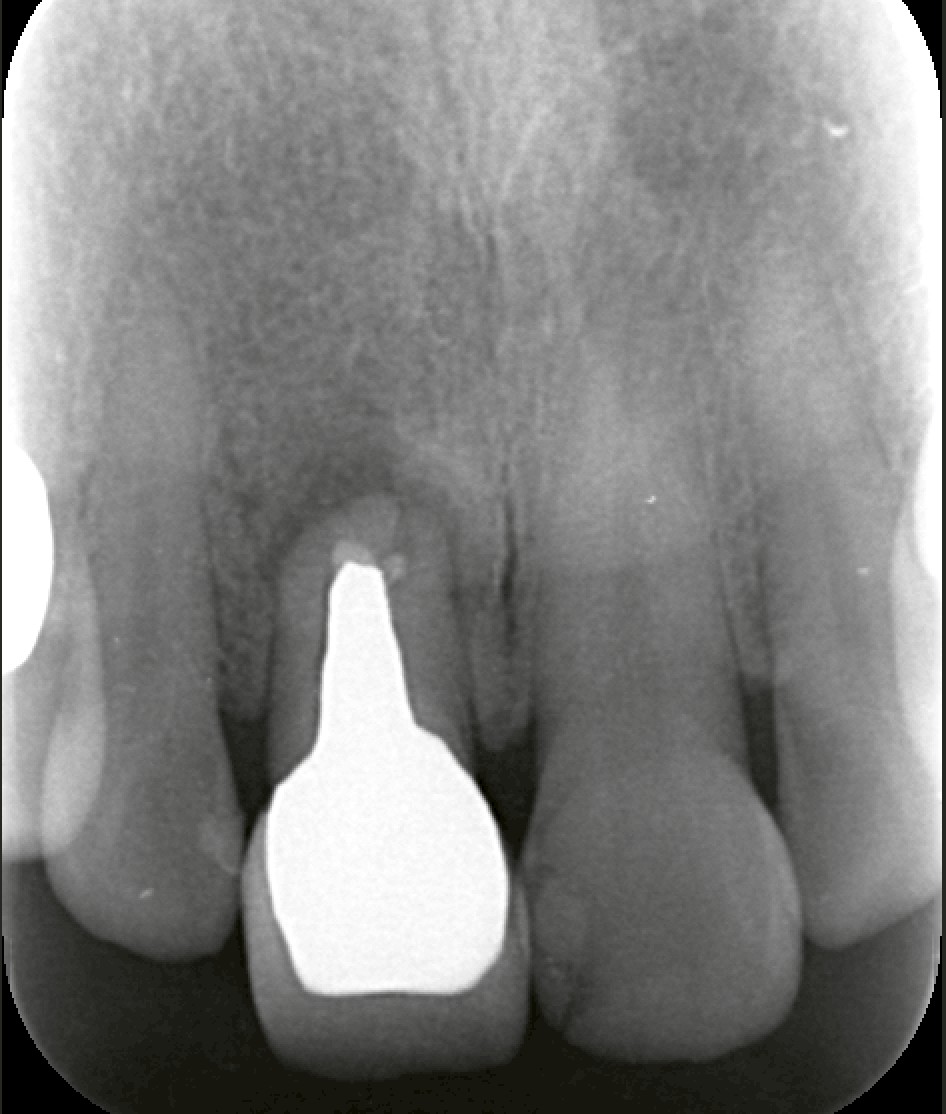

そこで、私たちは「インプラント=最善」ではなく、他の治療法も含めてトータルに検討しました。

今回のケースでは、接着性ブリッジでの回復をご提案しました。

接着性ブリッジのメリットは:

* 審美性を比較的シンプルに回復できる

* 手術の侵襲がなく、治療回数も少ない

* トータル的に患者様の負担が軽い

もちろん、ブリッジには支える歯への影響など注意点もありますが、今回は総合的に見てブリッジの方がベネフィットが高いと判断しました。